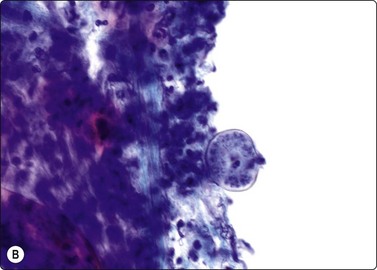

In fungal and cat scratch disease,40 suppurative granulomas with neutrophils interspersed among the epithelioid histiocytes in the granulomas may be present (Fig. 18.2).

image

Fig. 18.2 Suppurative granuloma

Neutrophils infiltrate epithelioid granuloma consisting of epithelioid histiocytes in background of neutrophils (Giemsa, ×600).